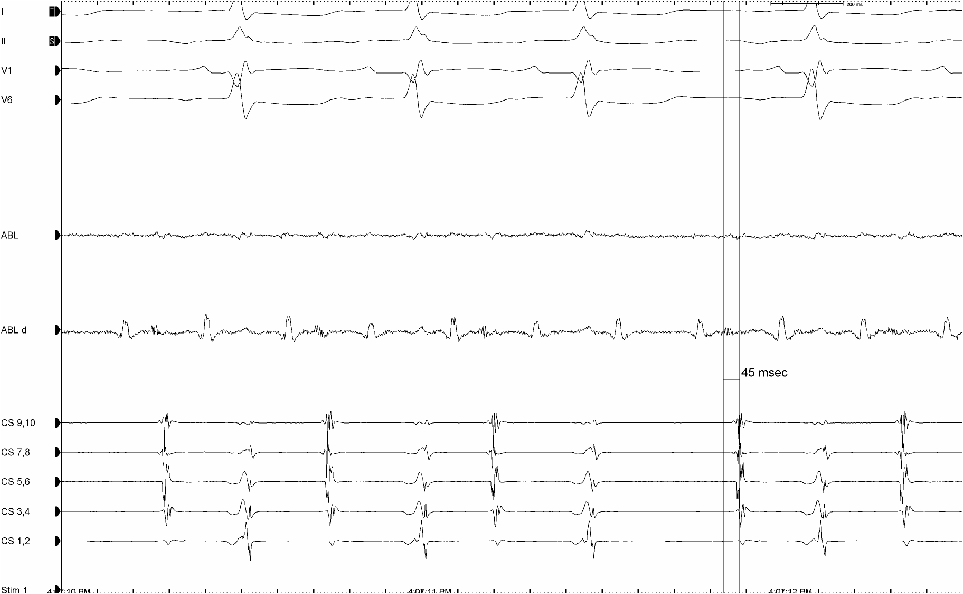

Transplant patient with A-tach coming from the native LA cuff. Note the fractionated signal represents the breakthrough site and only those cuff atrial electrograms associated with the fractionated signal get through to the CS and activate the ventricle. Ablation here eliminated the tachycardia by sealing the whole in the line.